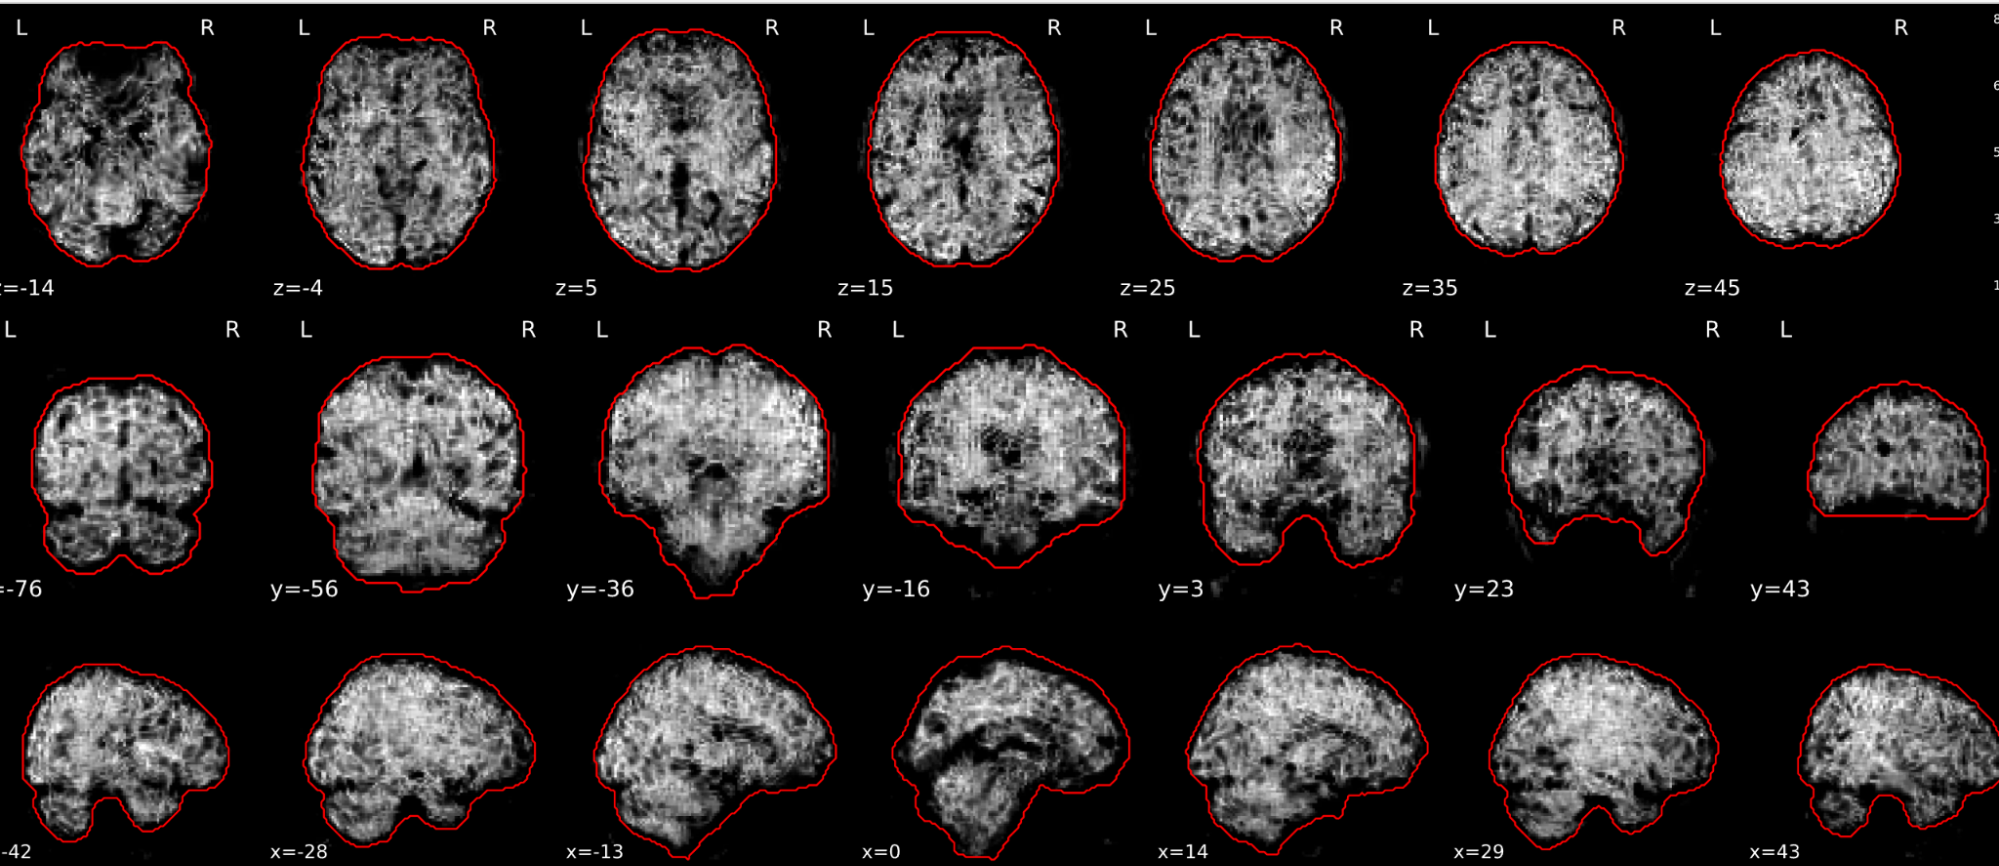

EPI tSNR

In the signal to noise ratio images of the resting state image the desired signal is compared to the amount of background noise. It is important to check all the views (sagittal, coronal, axial) because some artefacts (e.g., stripes) may be evident only in one particular view.

Example of a good subject

- Signal to noise is symmetrically distributed and there is no signal distortion

Example of a bad subject

- Asymmetry

- Potential signal distortion (might represent an artefact)

- Signal drop-out

- Stripes artefact

Clear large artefact (e.g., zebra stripes in example 1) are worth the exclusion of the subject. If you are unsure, check the other quality metrics for that subject to decide whether they should be excluded.

Summary

| good | bad |

|---|---|

| Symmetrical distribution of noise and signal | Asymmetry |

| No disruptions of the signal (no “black patches”) |

Potential signal disruptions (could be related to artefacts) |

| No stripes (sign of high motion) |

Signal drop |

| Stripe artefacts (“zebra” stripes due to motion) |